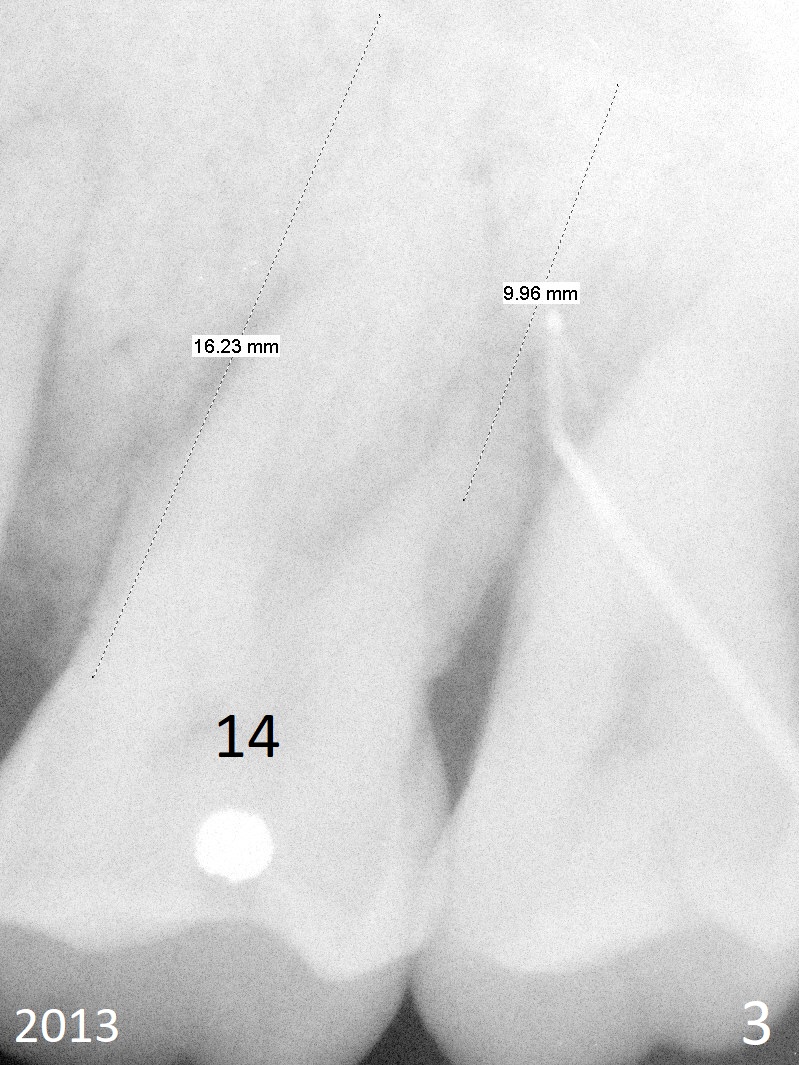

A 48-year-old woman has generalized moderate localized (#3,14) advanced periodontitis (Fig.1). The edentulous area at #6 has been restored. Now the tooth #3 has mobility III (Fig.2), while #14 has exfoliated (Fig.3,4). If the tooth #3 is symptomatic, extract it for immediate implant. Otherwise use Magic Split to initiate access and osteotomy expansion, followed by Magic Expanders (3.0 and 3.8 mm) or Magic Sinus Lifter. Insert Tatum tapered taps. If the gingiva is excessively long, switch to UF implant for mill abutment.